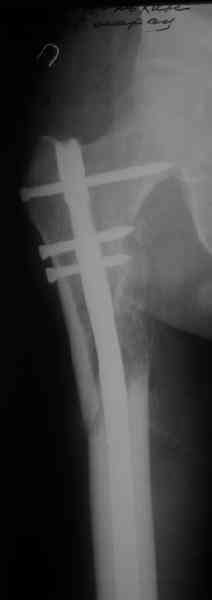

СМ> Если имеются под рукой Р-снимки, продемонстрируйте, плиз.

Вот несколько. С тисками и трубой на днях сделаем.

Саша, последний штифт, пожалуй, перегнули?

> Саша, последний штифт, пожалуй перегнули?

Там заход сделан как для прямого штифта, не через вертел.